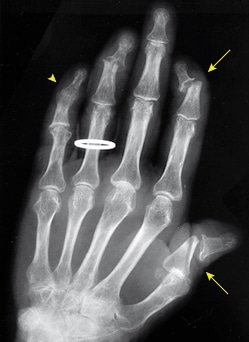

Imagem III: Artrite psoriática associada à anormalidade do tipo lápis-em-copo nas articulações interfalângicas distais (DIP) do primeiro e segundo dedos (setas), além de alterações precoces na articulação DIP do quarto dedo. Outras alterações incluem anquilose na articulação DIP do quinto dedo (ponta de seta) e destruição do punho. Fonte: Gladman, Ritchlin, 2024